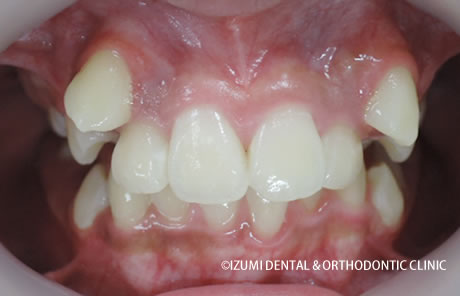

この方は子供の矯正終了一年後から歯列矯正の治療に入られましたので、その後も見てみましょう。

子供の矯正終了から1年後 歯列矯正開始(歳何ヶ月)

よくこんなとこらから犬歯がはえてきたとびっくりされる親御さんがいらっしゃいますが、これは以下のように、結構簡単に治ります。